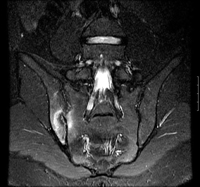

- MRI sacrum:

sacroiliitis